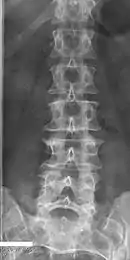

Block vertebrae of the cervical spine (vertebrae 4 and 5). Probably based on degenerative or inflammatory changes.

Several congenital block vertebrae in the transition from the thoracic to the lumbar spine and hemivertebrae.

Congenital block vertebra in the lumbar spine (partial vertebrae 3 and 4). The rear portion of the disc still exists.